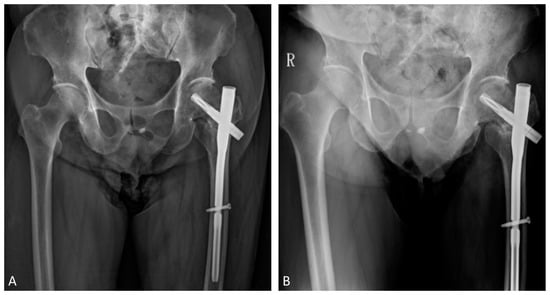

2. Case Report